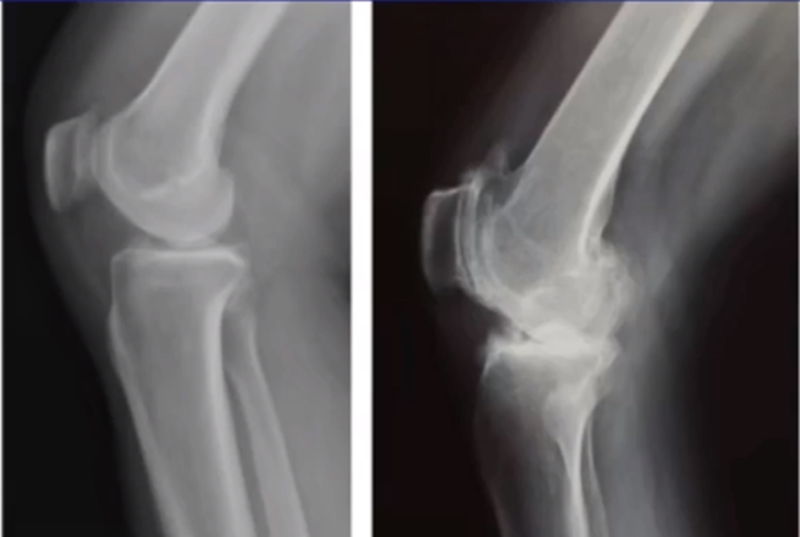

三、单髁置换的适应证——标准侧位片

标准侧位片,内外髁完全重叠,胫骨平台也一样,如果检查不标准,X线片结果会影响判断。

侧位片可以显示胫骨平台磨损部位,在判断前交叉韧带功能是否完好方面有重要意义。当磨损部位在前方或中前方,没有延伸到胫骨平台后缘时,说明前交叉韧带功能正常;当磨损部位延伸到胫骨平台后方,甚至引起后方半脱位状态时,说明前交叉韧带功能缺失或损害,此时不适合做单髁。

AMOA的侧位X线表现

ACL功能完好是单髁重要的适应证。当ACL失去功能,导致后方软骨磨损或者骨缺损,此时为整个内侧或全间室的骨关节炎,不是单髁的适应证了。

在牛津单髁标准教程里,表明前交叉韧带与后交叉韧带都应该保持功能正常,才是单髁的适应证。